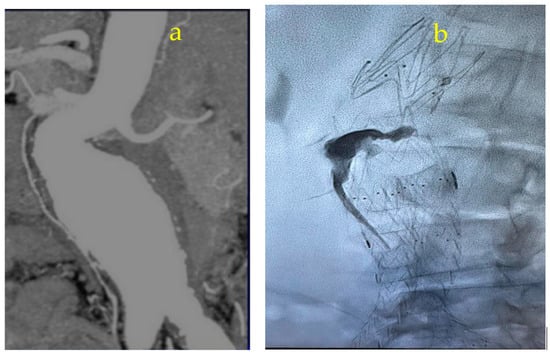

Appendix A.2. Clinical Case 2: Treatment of Endoleak Type II Inferior Mesenteric Artery